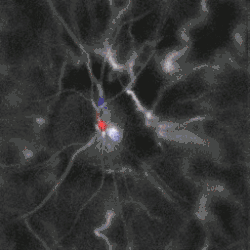

Blood flow in the retina and choroid in the optic disc region can be revealed non invasively by near-infrared laser Doppler imaging.[4] Laser Doppler imaging can enable mapping of the local arterial resistivity index, and the possibility to perform unambiguous identification of retinal arteries and veins on the basis of their systole-diastole variations, and reveal ocular hemodynamics in human eyes.[5] Furthermore, the Doppler spectrum asymmetry reveals the local direction of blood flow with respect to the optical axis. This directional information is overlaid on standard grayscale blood flow images to depict flow in the central artery and vein.[6]

![Local direction of blood flow with respect to the optical axis revealed by the Doppler spectrum asymmetry in out-of-plane retinal vessels by holographic laser Doppler imaging.[6]](./_assets_/LaserDopplerHolographyRetinaSpectralAsymmetry.gif) Local direction of blood flow with respect to the optical axis revealed by the Doppler spectrum asymmetry in out-of-plane retinal vessels by holographic laser Doppler imaging.[6] Local direction of blood flow with respect to the optical axis revealed by the Doppler spectrum asymmetry in out-of-plane retinal vessels by holographic laser Doppler imaging.[6]